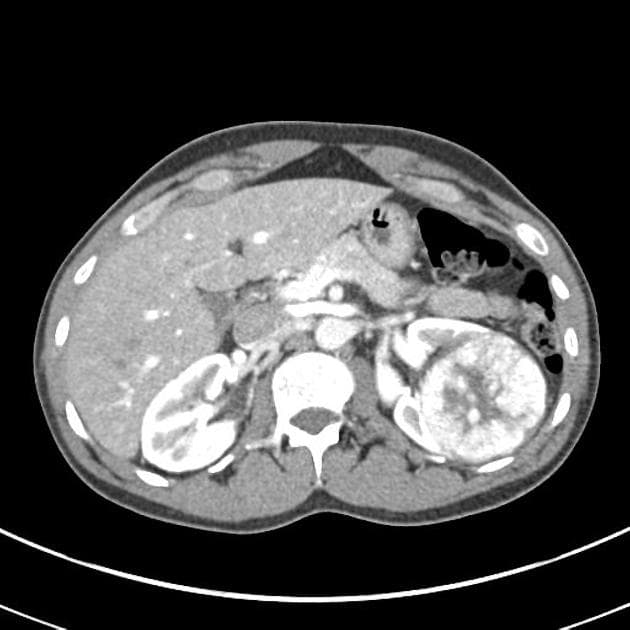

Axial renal excretory phase

U oncocytoma trên thận móng ngựa

Đái máu không đau, nội soi bàng quang âm tính. Chụp CT để loại trừ tổn thương đường tiết niệu trên.

Thận móng ngựa.

Một tổn thương khối đặc, tăng mật độ không đều, một phần lồi ra ngoài (exophytic), kích thước khoảng 6,0 cm, nằm ở mặt sau dưới của phần nối (isthmus), lệch trái so với đường giữa.

Một nốt đặc nhỏ lồi ra ngoài (exophytic), kích thước 12 mm, nằm ở mặt bên của cực trên phần thận phải.

Nang loại Bosniak 1 nằm ở mặt trước của phần nối (isthmus).

- Thận móng ngựa với hai tổn thương tăng mật độ, ban đầu nghi nhiều khả năng là u tế bào ống thận (renal cell carcinoma – RCC), phân độ hình ảnh T1bN0M0 (tổn thương lớn) và T1aN0M0 (tổn thương nhỏ).

- Tổn thương lớn đã được cắt bỏ, kết quả giải phẫu bệnh lý cho thấy oncocytoma.

- Oncocytoma là một khối u (tumor) lành tính của thận, thường bắt chước hình ảnh của u tế bào ống thận (RCC) trên các phương tiện chẩn đoán hình ảnh, gây khó khăn trong phân biệt nếu không có xác nhận bằng mô bệnh học.

Oncocytoma trên thận móng ngựa (oncocytoma in horseshoe kidney)